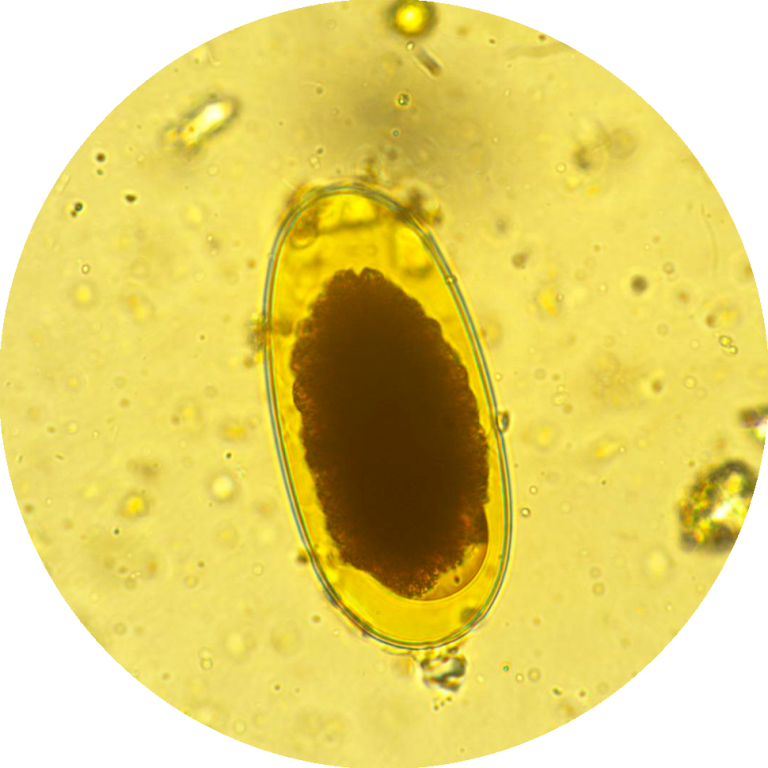

Aprofundar a Identificação Microscópica: Fornecer conhecimentos detalhados sobre a morfologia e ciclos de vida dos principais parasitas encontrados em amostras sanguíneas (ex: Babesia, Anaplasma, Dirofilaria) e fecais (ex: ovos e oocistos de nematóides, cestóides, trematóides e protozoários), utilizando as modalidades de campo claro e campo escuro.

A microscopia continua a ser a técnica laboratorial de eleição para o diagnóstico de infeções parasitárias, sendo as técnicas de coloração, usadas na preparação da amostra, o fator decisivo para um diagnóstico correto e eficaz.